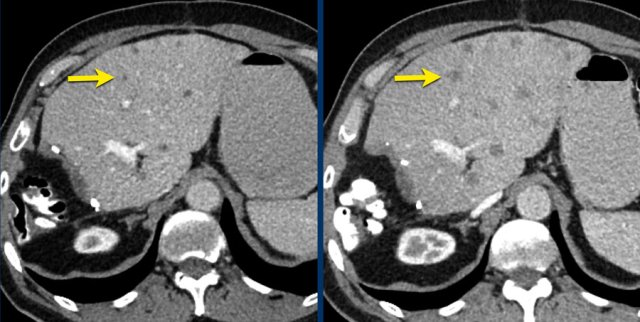

Here another example of progression of non-target lesions.

CT images in a 73-year-old male with progressive liver metastases of colorectal carcinoma.

At baseline the liver metastases were too small to be used as target lesions and consequently they were used as non-target lesions.

At follow up there is unequivocal progressions.

Unequivocal progression of non-target lesions means progressive disease, even if there is partial response or even disappearance of the target lesions.